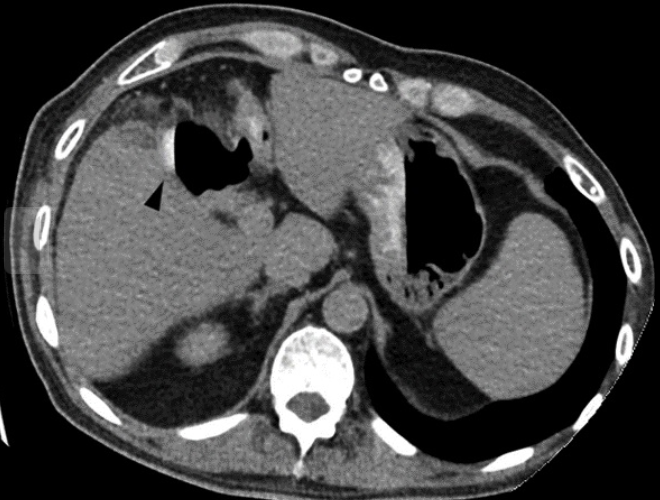

Homem, 74 anos, fibrilação atrial.

Dor abdominal aguda.

Infarto tromboembólico da artéria renal direita.

Região hipodensa com defeito de realce em forma de cunha.

Sinal do realce cortical ocorre geralmente após 24 horas do infarto e consiste no realce da margem periférica do rim na fase nefrográfica, no contexto isquemico. Ocorre em cerca de 50% dos casos.